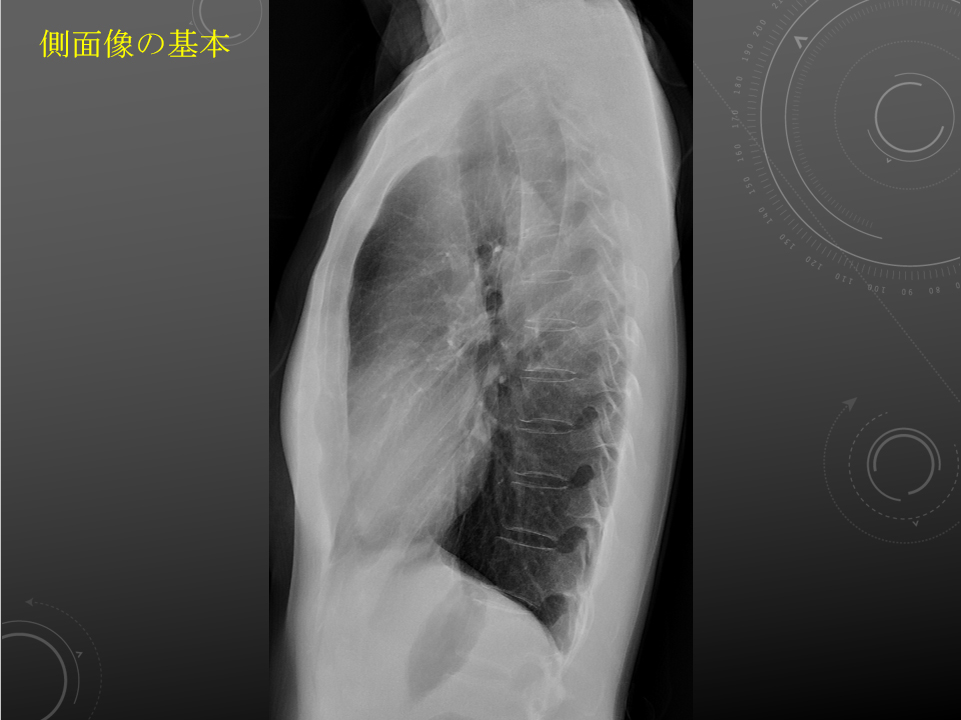

胸部:吸気/呼気、側面

気道の透亮像の濃度は前部(右肺動脈+左右の上肺静脈)が後部(左の肺動脈)よりも高いのが普通である。

正常の写真を載せてもいいかもしれない…